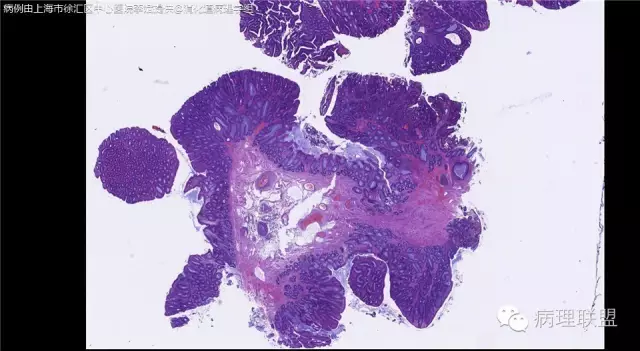

男,72岁,距肛门口30cm息肉。大体:灰白结节1.5*1*0.8cm拟发管状腺瘤并部分区高级别,请各位老师指导!(病例由上海市徐汇区中心医院 李斌 提供,致谢!)

这一例有两种不同看法,按WHO标准,为高级别,按实际工作,要发粘膜内癌。WHO第三版与第四版均提出,侵犯至粘膜下层才能诊断为癌,声称结直肠粘膜内没有淋巴管,发生转移的概率较小,但是粘膜内有血管,肿瘤侵出粘膜腺体基膜以外,就能侵犯血管,照样可以发生血道转移。文献报告与我们的工作实践,发现腺瘤、高级别(没有侵出基膜)的患者,同样有发生血道转移。因此,我们废弃了这一条WHO标准(不是所有的WHO标准都是一定要执行的)。只要异型增生腺体呈毛刺状、迷芽状侵出粘膜腺体基膜,位于粘膜肌层以内,就发粘膜内癌。

@李斌 结肠腺瘤这例我认为已经有黏膜下浸润了,因为有些腺体间的间质已经不是固有膜间质而是促结缔组织增生反应的间质了。但即使有浸润癌,如果息肉完整摘除、癌成分分化好、没有脉管瘤栓、浸润癌距切缘大于1mm(日本标准还要看浸润癌超出黏膜肌深度和肿瘤出芽情况),也不需要进一步治疗。所以,对于这类可能存在争议的病变,特别是息肉已经完整切除的病例,诊断的关注点就应该放在寻找需不需要进一步治疗的证据上了。@邓永键 2010版WHO在腺瘤部分的陈述中已经写出对于有局灶浸润性生长的病例也可以称黏膜内癌,他们在悄悄的让步。